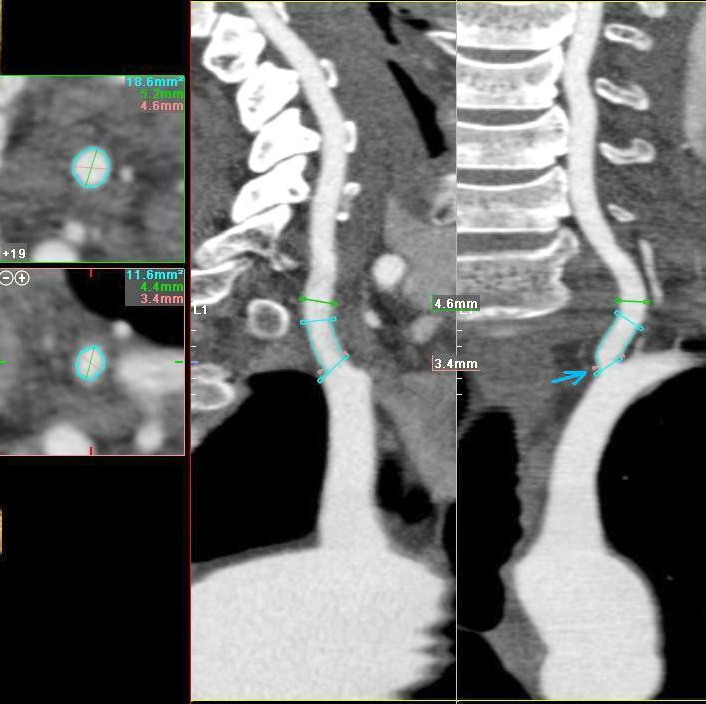

Мужчина, 62 года. Перенес ишемический инсульт в бассейне правой средней мозговой артерии.

На КТ-ангиографии выявлена окклюзия правой внутренней сонной артерии в области развилки в виде паламени свечи (красная стрелка), стеноз высокой степени в устье правой вертебральной артерии (желтая стрелка), небольшой перегиб в устье левой вертебральной артерии (голубая стрелка).

Вы отчасти правы. Инсульт пациент перенес давно, тогда не было возможности ни диагностировать, не лечить. Сейчас ему планируют установить стент в правую позвоночную артерию.

Больному успешно установлен стент в устье правой вертебральной артерии.